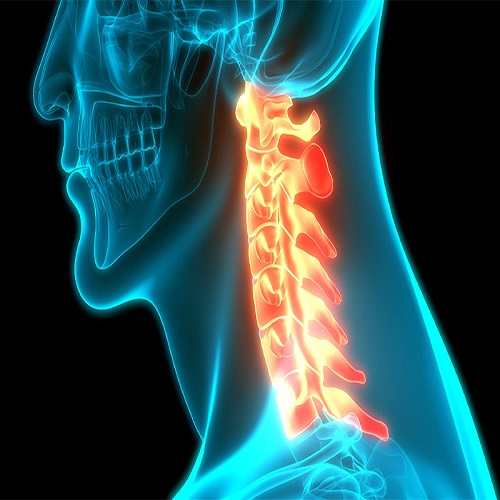

دیسک گردن

دیسک بین مهرهای ساختاری ژلاتینی است که مانند ضربهگیر عمل کرده و فشار را بین مهرهها توزیع میکند. این ساختار کمک میکند تا مهرهها به نرمی و بدون اصطکاک زیاد بر روی یکدیگر حرکت کنند. در واقع، دیسک نوعی مفصل با ساختاری ویژه است که به حفظ انعطافپذیری و پایداری ستون فقرات کمک میکند.

یکی از مشکلات شایع مرتبط با دیسک، بیرونزدگی دیسک گردن است. این وضعیت میتواند بر اثر فشارهای طولانیمدت یا ناگهانی به گردن، یا به دلیل فرسایش و سائیدگی مفاصل ناشی از افزایش سن رخ دهد. معمولاً پس از سن ۳۵ سالگی، مایع ژلاتینی موجود در دیسکها بهتدریج کاهش مییابد و خشک میشود. این کاهش آب، انعطافپذیری دیسک را کم میکند و موجب سختتر شدن حرکت مهرههای گردن میشود.

هنگامی که دیسک از محل طبیعی خود خارج شود و به ریشههای عصبی یا نخاع فشار وارد کند، این وضعیت به عنوان بیرونزدگی یا فتق دیسک گردن شناخته میشود.

علت بیرون زدگی دیسک گردن

در قسمتهای قبلی اشاره کردیم که بیرون زدگی دیسک میتواند دلایل مختلفی داشته باشد.

از وارد شدن فشار زیاد و ناگهانی گرفته تا افزایش سن و مسائل ژنتیکی. در این بخش به طور مفصل به هر یک از دلایلی که زمینه ابتلاء به دیسک گردن را فراهم میکند میپردازیم.

وارد شدن فشار به گردن

بعد از عواملی مثل وراثت و سن، وارد شدن فشارهای فیزیکی مهمترین عامل در آسیب رسیدن به دیسک و بیرون زدگی آن هستند.

بلند کردن یک جسم سنگین،خم شدنهای طولانی، نشستن طولانی مدت پشت میز نیز می تواند به مهرههای گردن فشار وارد کند.

انجام ورزشهای غیر اصولی، بد نشستن و بد خوابیدن و قرار گیری در وضعیت نامناسب میتواند منجر به بیرون زدگی دیسک گردن شود.

چرا بیرون زدگی دیسک گردن می تواند خطرناک باشد؟

باید بدانید که ستون فقرات که نخاع از داخل آن عبور میکند، شامل تعداد زیادی عصب حسی است که وظیفه کنترل حرکت دست ها و قسمتهای مختلف بدن را بر عهده دارند.

همچنین در قسمت گردنیِ نخاع الیاف عصبی وجود دارند که به سمت پایین امتداد یافته و مسئول ایجاد حس و کنترل ادرار و مدفوع در قسمت پایینتنه هستند.

به همین دلیل دیسک گردن که درست در مجاورت نخاع و عصبهای اصلی بدن است، موضوع بسیار مهمی است که در صورت بروز علائم حتما باید پیگیری و توسط پزشک متخصص بررسی شود.

چراکه در صورت سهل انگاری و عدم رسیدگی میتواند باعث آسیبهای جدی به نخاع و اعصاب بدن شود.